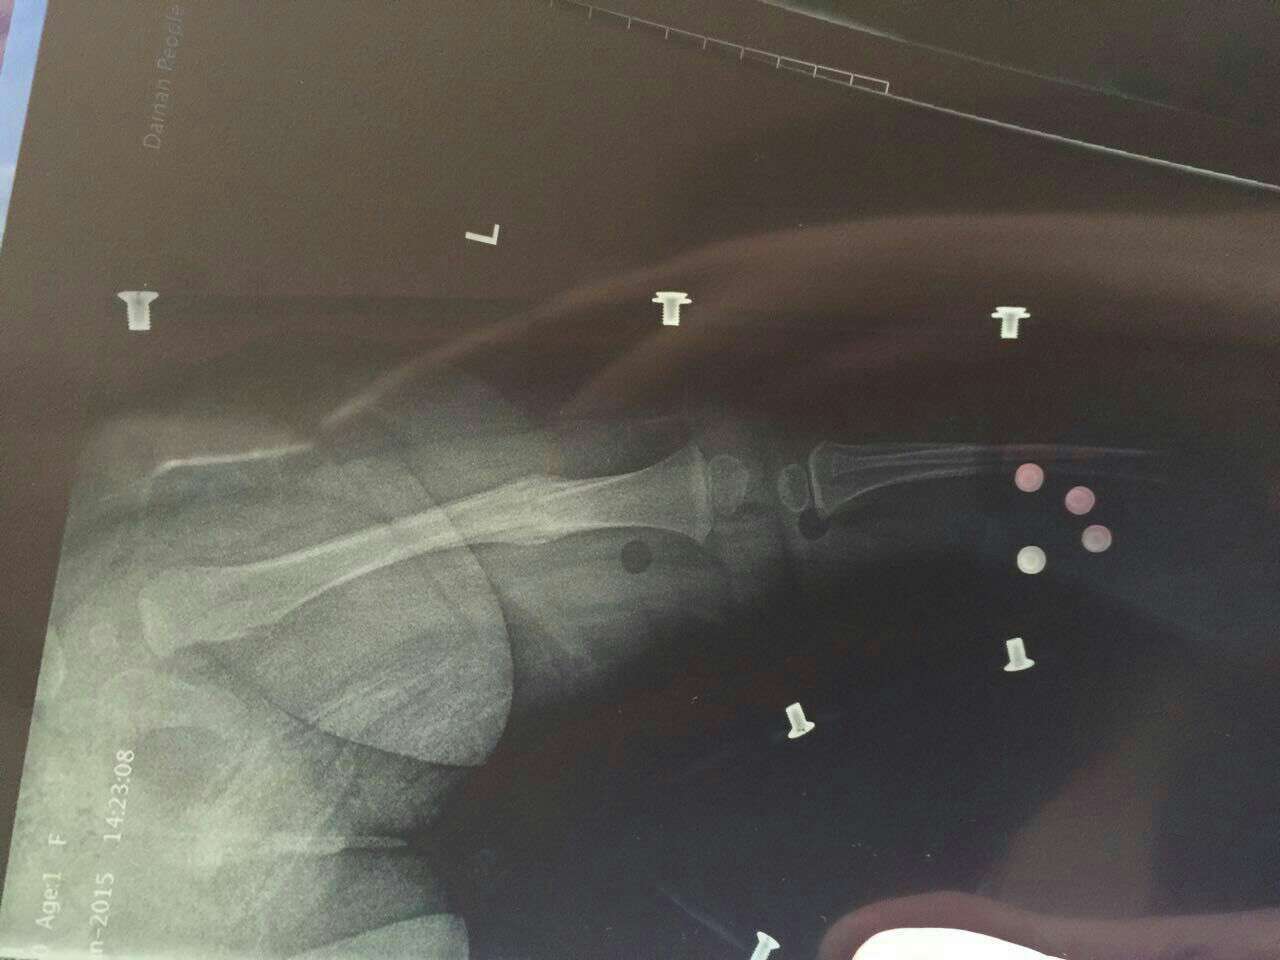

九个月宝宝股骨骨折出大量骨痂形成,可以拿掉支架了吗? 在医院牵引了23天,然后上了支架回来已经22天多,什么时候可以拿掉支架?可以竖着抱吗?什么时候能学走路? 点击展开 匿名用户 2015-01-23 10:53 相关问题 2岁女孩股骨近端骨折后牵引半月dr报告对位对线可,有骨痂影,对以后有没有影响? 我左骰骨骨折 现在手术后已经九个月 我现已上班,是坐着工作,前几天做X线复查,有较多骨痂影,未见内 无骨折症状,带固定支架后骨骺分离